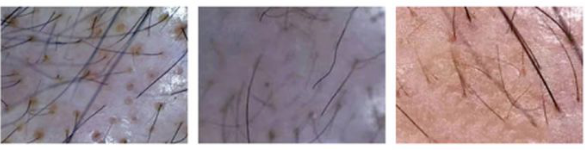

Q:萎缩毛囊和闭合毛囊

萎缩毛囊是可以长出头发来的,但头发通常偏细、软,参差不齐,容易脱落,萎缩越严重,头发质量越不好。

①油脂性毛囊 ②萎缩的毛囊 ③濒临坏死的毛囊

斑秃、雄脱、休止期脱发等都可能使毛囊萎缩、闭合...毛囊呈现的状态都一样。

不同头皮问题可以通过头皮智能检测仪设备查看,镜检下不同原因造成的脱发有不同呈现。

毛囊检测不仅可以分辨出一些明显的头皮疾病,还可以很直观的看到:头皮的颜色、毛囊萎缩坏死情况和毛囊分布密度,哪些头发即将脱落,哪些是新生长出来的头发等等。